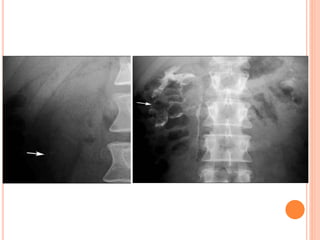

• #34 PERSISTENT NEPHROGRAM= obst. Rapid sequence RAS

• #36 Immediate dense persistent ATN

• #37 CIN

• #46 Tubular ectasia meduallry sponge k